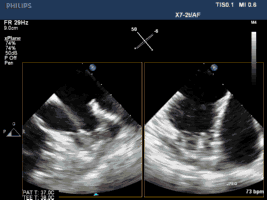

3. 经右侧股静脉置入SL1鞘管,沿鞘管送入房间隔穿刺针,食道超声下见左心耳血栓

4. 超声指导下成功行房间隔穿刺,将鞘管推进至左房后予肝素7000U,SL1 导丝送左房后,超声下测左心耳开口大小后选用LAmbre 左心耳封堵器(20-26mm)